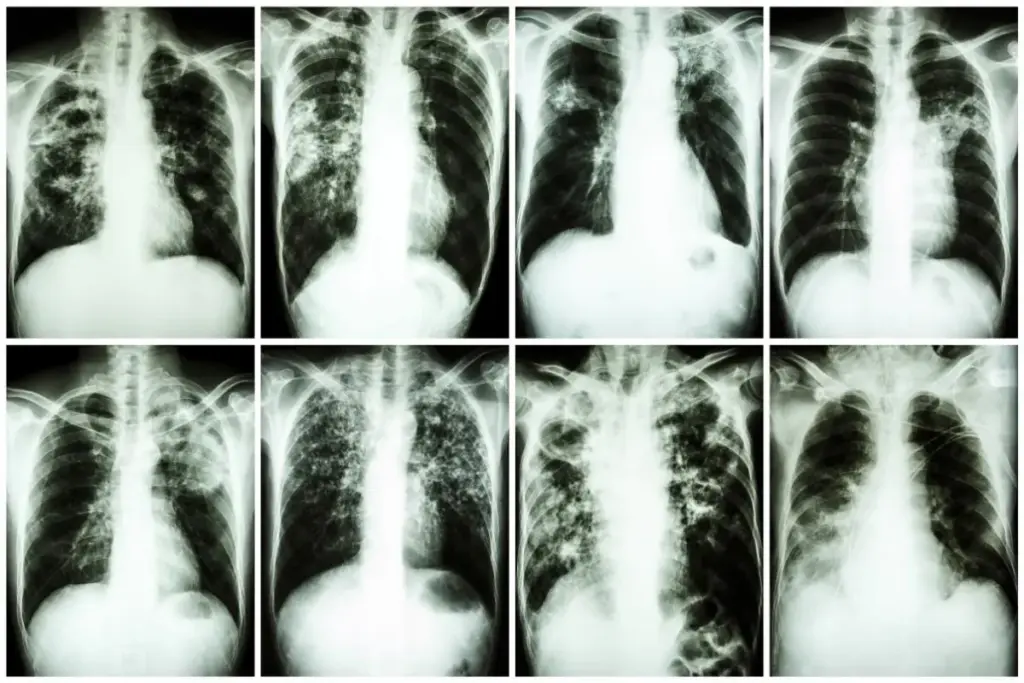

Even though the lungs are affected in most cases, sarcoidosis is a disease that can involve the whole body.

The definition of the disease encompasses its potential to affect multiple systems simultaneously or sequentially. It is not merely a lung disease but an immunological disorder that manifests prominently in the thorax.

The lungs and chest lymph nodes are affected in more than 90 percent of patients. However, the skin, eyes, and liver are also frequently involved.